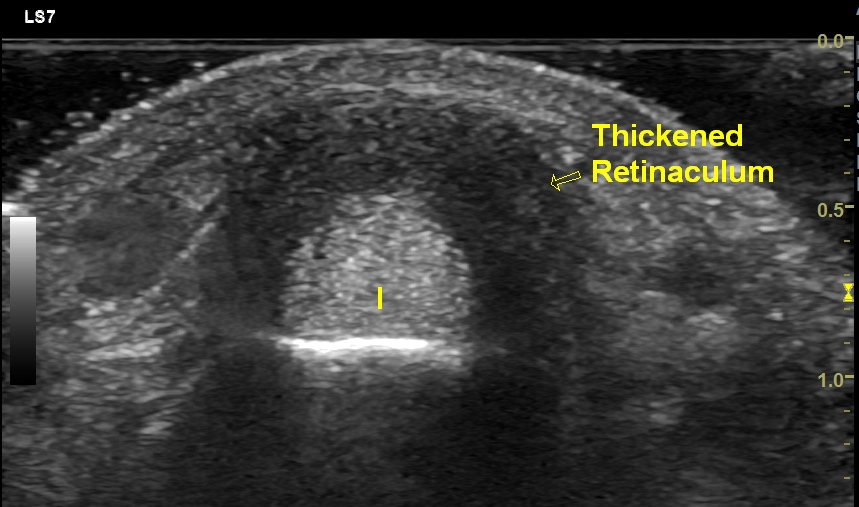

Ultrasound (US) imaging shows diffuse thickening of the extensor retinaculum over abductor pollicis longus (APL) and extensor pollicis brevis (EPB) tendons. Mild effusion with synovial hypertrophy is seen in the APL & EPB tendon sheath. Power Doppler shows increased vascularity in the thickened synovium. Dynamic imaging shows restricted gliding of APL & EPB tendons below the thickened extensor retinaculum. Based on the clinical presentation & imaging findings, a diagnosis De Quervain’s tenosynovitis was made.